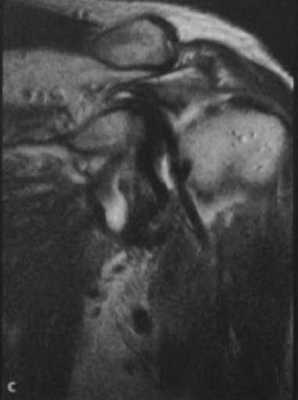

(с) Фронтальная МРТ. Часть разорванного сухожилия надостной мышцы «плавает» точно сверху и латерально по отношению к сухожилию двуглавой мышцы.